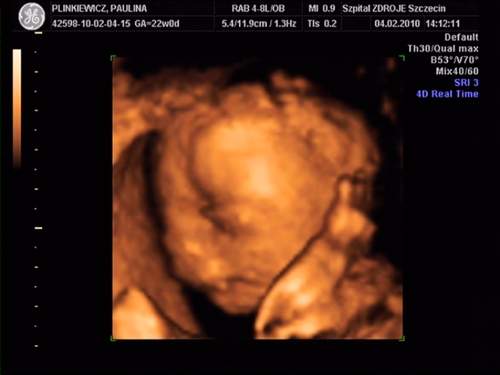

MAleńka jest super....Rozumiem że to imienniczka mojej córci - Pola!!!! Jest cudowna...Gratuluję!!!!Moja córeczka:

na drugim zdjęciu ziewa :-) a na ostatnim trzyma się za uszko:-)